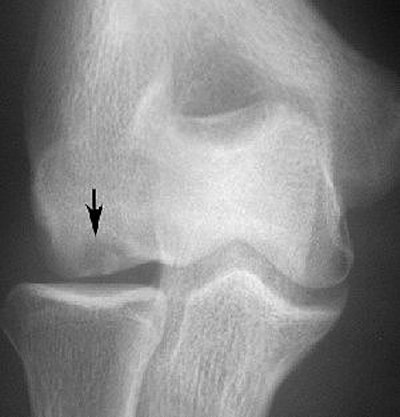

|  |

| An 18-year-old man with lateral elbow pain for four months and surgically proven unstable osteochondritis dissecans of capitellum. Anteroposterior radiograph of elbow shows osteochondritis dissecans lesion (arrow) as focal well-defined area of subchondral radiolucency. Kijowski R and De Smet AA, "MRI Findings of Osteochondritis Dissecans of the Capitellum with Surgical Correlation" (AJR 2005; 185:1453-1459). |